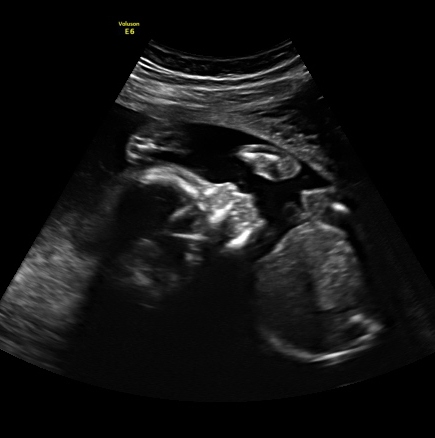

I am loving all the bumps and boobs Here is a pic of me at 20 weeks the other day wearing the sweater dress I had a meltdown about because I felt gross in it. I had my A/S today and everything looked perfect. Our little guy was not very cooperative though so I couldn't get a 3D pic. My sister is an ultrasound tech so she will take me in and scan me another time to get some good face pics. Here is his profile with a knee by his mouth and a good one of his feet. He was curled up with his arms and legs covering his face when they tried to do 3D. Little stinker!

I had my A/S today and everything looked perfect. Our little guy was not very cooperative though so I couldn't get a 3D pic. My sister is an ultrasound tech so she will take me in and scan me another time to get some good face pics. Here is his profile with a knee by his mouth and a good one of his feet. He was curled up with his arms and legs covering his face when they tried to do 3D. Little stinker!